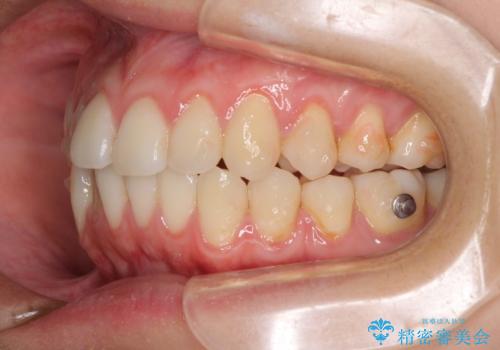

- 上下前歯のデコボコを気にして来院された患者様です。

インビザラインによる上下歯列の側方拡大と後方移動、IPR(歯と歯の間を削る)にるスペースの獲得により歯列を整えることとしました。

1日22時間の装着時間をしっかり守ってくださったので、予定していた1年よりも早く治療を終えることができました。

インビザライン矯正特有の奥歯がしっかりと咬合しない感覚も改善され、大変満足していただきました。